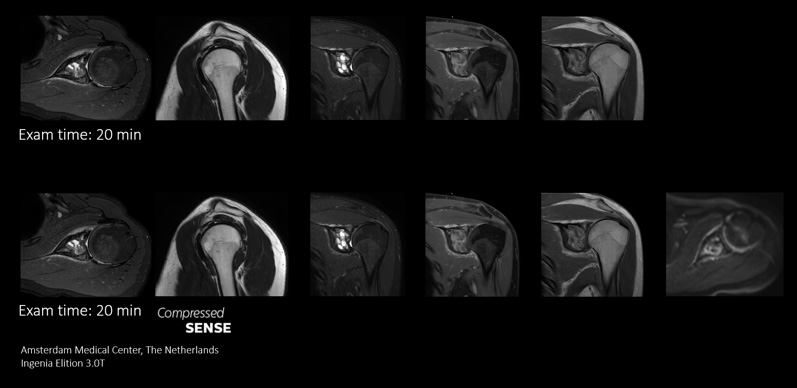

More information in the same time slot

Compressed SENSE gives MRI departments the flexibility to acquire as much relevant information as possible within the MRI scan time slot. Its speeds allows extra routine and functional sequences to be added to enhance diagnostic information.

This case demonstrates the ability to add additional sequences within the same time slot to enhance your diagnostic confidence. Besides traditional TSE sequences, you can now add a functional DWI sequence within the same timeslot, providing additional information for you to base your diagnosis on.